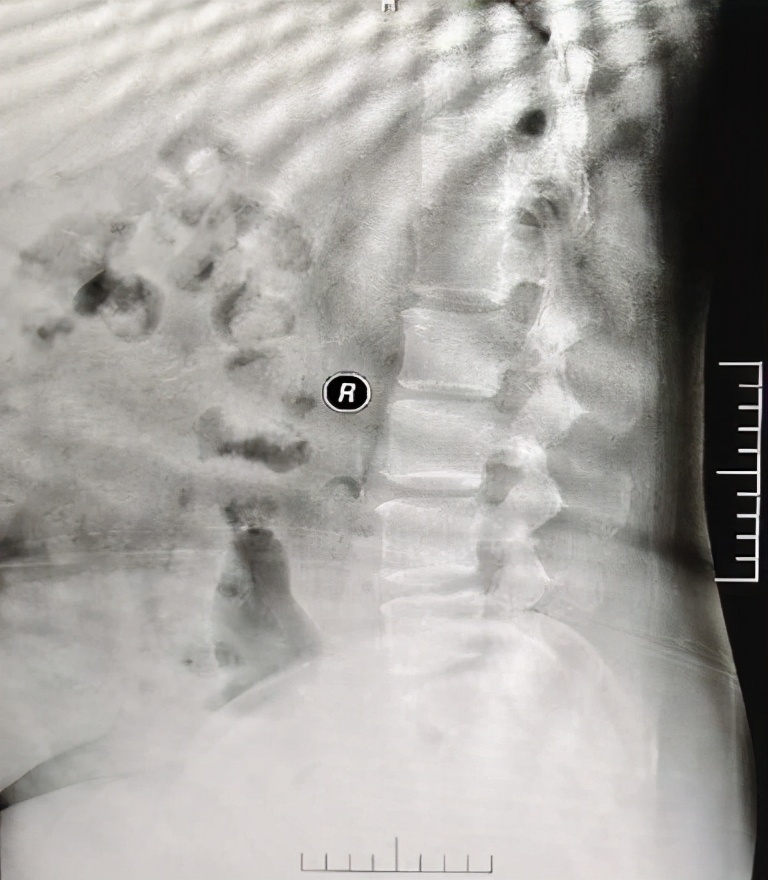

腹部侧位片上已有腹主动脉钙化表现

2012.9左女士在我们科诊断慢性肾脏病5期,开始行血液透析治疗,每周三次透析,刚刚进入透析状态时,左女士主要表现为低钙、高磷、高PTH,PTH最高达到2000+,但是因为没有症状,所以左女士并没有太在意,每日饮食丝毫不注意,虽然医护人员多次劝导,但是成效甚微。到了2014年底,左女士逐渐出现了Ca、P、PTH代谢障碍带来的一系列症状,包括不宁腿综合征、皮肤瘙痒等情况,评估腹部侧位片检查已经出现了血管的钙化,此时的左女士才开始意识到问题的严重性,在医护人员的共同协助下,开始了漫长的CKD-MBD治疗之路。首先在饮食上,严格限盐限磷,注意低盐低脂优质蛋白的饮食,其次在加强透析治疗的基础上联合药物治疗,包括应用碳酸镧、帕立骨化醇、西那卡塞等药物进行Ca、P、PTH的联动管理,逐渐的左女士的血Ca、血P、血PTH降至正常范围。伴随着Ca、P、PTH的达标,左女士的睡眠问题、不宁腿、皮肤瘙痒等情况均得到改善。